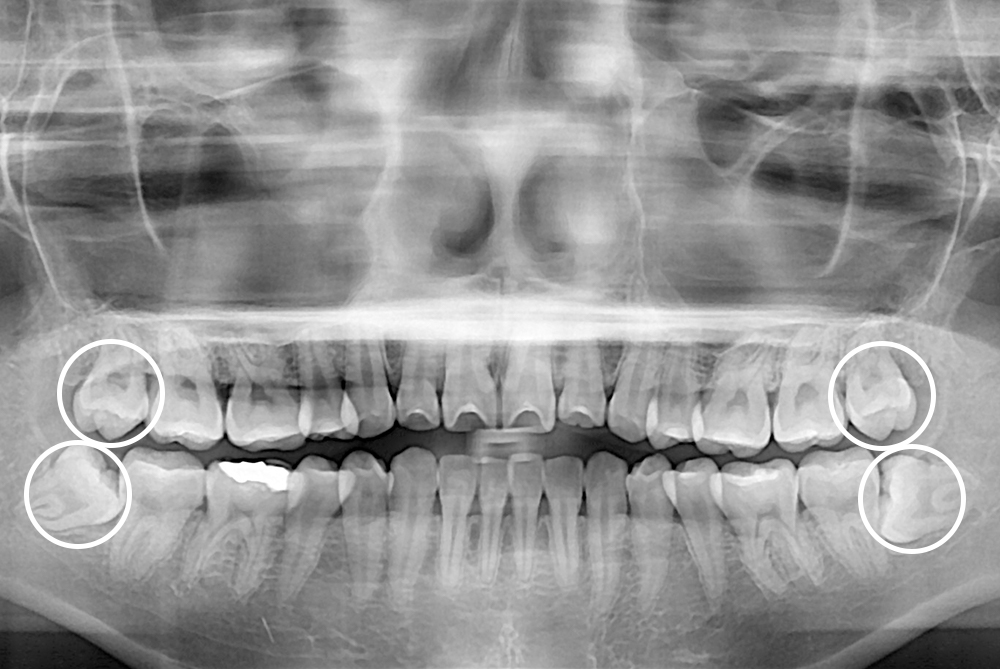

10135 김희경 후 2.jpg

치료후 : 2016-08-06

세종치과는 구강악안면외과학 박사이신 원장님이 발치하는 치과입니다.